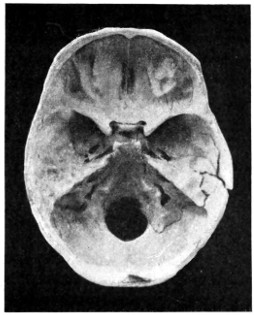

29 A and B. The base of the skull and the base as seen on transillumination 70, 71

30. Plan of the base of the skull 77

50 A and B. The inner aspect of the skull and the same seen on transillumination 137